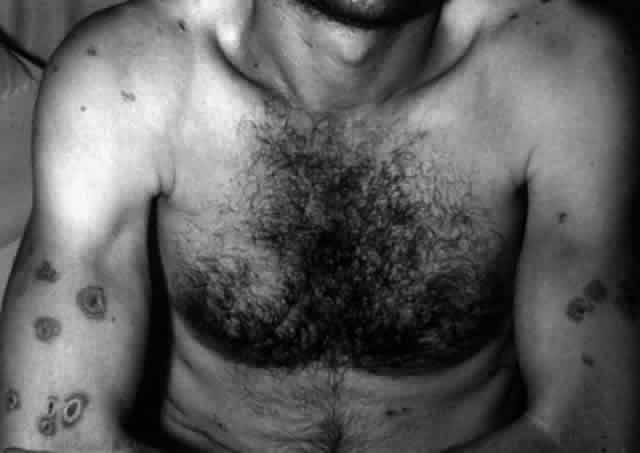

Pemphigus (from the Greek meaning puff or blister) comprises a group of autoimmune vesiculobullous eruptions of the skin and mucous membranes that are seen primarily in middle-aged people, with both sexes being affected equally.3 Involvement of mucosae may occur as the initial manifestation in as many as 25% of cases, and it occurs at some point during the course of disease in 95% of cases.4 Pemphigus vulgaris and its variant, pemphigus vegetans, constitute a more acute form of the disease in which the earliest lesions appear in the oral mucosa and are then followed by a bullous eruption of the skin over the trunk and extremities within 4 to 12 months (Fig. 1). This form of pemphigus was almost uniformly fatal prior to the use of systemic corticosteroid therapy. The mortality rate was reduced to approximately 40% by the use of steroids and has been further reduced to 5% by the addition of immunosuppressive chemotherapeutic regimens for the most difficult cases. Pemphigus foliaceus and its variant, pemphigus erythematosus, follow a more chronic but benign course. Mucosal lesions are unusual in this form, which is primarily an exfoliative dermatitis.3

Erythema multiforme (EM) is an acute inflammatory disease affecting primarily skin and mucous membranes.66 Major and minor variants exist, and it is the former, also known as Stevens-Johnson syndrome (SJS), that is of most concern to ophthalmologists.67 Prodromal symptoms of SJS include general malaise, myalgias, and fever.68 Skin lesions develop by 10 days to 4 weeks after the onset of the prodrome; they tend to be annular in shape (“iris lesions”) but may be maculopapular or bullous. Most commonly, involvement is limited to the skin of the dorsum of the hands and feet and the palms and soles. Later, the limbs, trunk, face, and neck may become involved (Fig. 14). EM major or SJS may be fatal, either from the systemic, visceral involvement of the disease or from complications arising from the extensive exfoliation of skin, producing consequences similar to those seen in patients with third-degree burns. The mortality rate is reported to be between 5% and 15% of cases, and 20% of cases recur.66